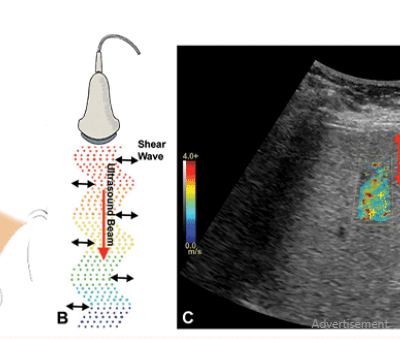

USG Breast